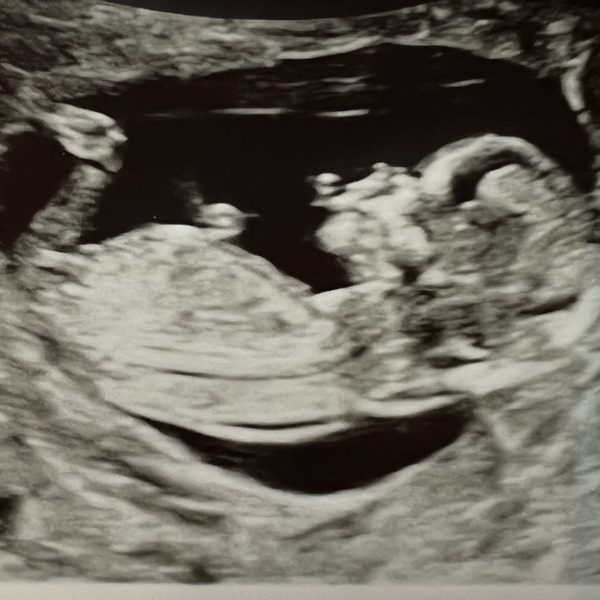

We’ve had our scan and all is looking good.

Thought I’d share it with you all. Due date is 31st July.

We were both quite nervous but the sonograper was lovely.

She said all is looking well. And that the baby has a cute face. I imagine she says that to everyone, but it was still nice!

It was incredible to see the little one moving around in there. And see all of it’s fibgers and toes. We feel excited but are very much taking this stage by stage.

We chose to have the tests available. There’s no sign of Down’s syndrome from the scan, but we should know within 4 days if the bloods indicate a high chance of this, Edwards or Patau.

Thanks for the update OP, so glad all is well. And thanks for sharing your scan picture, it looks amazing and very clear. So so chuffed for you 💐 x